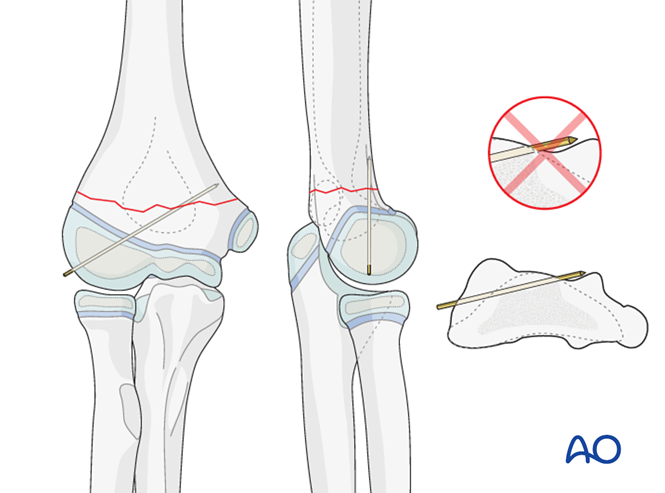

一,儿童骨化中心